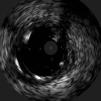

The procedure was performed by radial approach using a 7F guiding catheter. Plaque preparation was performed with rotational atherectomy using a 1.5 mm burr (Figure 3) and further predilation with a cutting balloon (3-3.5 mm). After balloon dilatation, rupture of severely calcified plaque was detected by IVUS (Eagle Eye; Volcano Corporation, Rancho Cordova, CA, USA), so we proceeded to implant a 3.5 mm×20 mm CRE 8 DES in the LM and LAD (Figures 4 and 5). At this point the wire was accidentally pulled back and was reintroduced into the LM and LAD. Post-dilatation was performed with a 4 mm non-compliant balloon. IVUS examination with manual pull-back at this stage revealed that the proximal part of the stent in the LM had been crushed as a result of lateral reintroduction of the wire through a proximal stent strut. The patient remained stable with normal flow in the LM and LAD. Guided by IVUS, a second wire (Sion, Asahi Intecc, Japan), with a 30° bend in its 1 mm distal tip, was introduced within the crushed stent segment (Figure 6). Once the guidewire was positioned inside the stent, progressive dilations with small (1.5 mm) to large (4 mm) balloons were performed until the stent regained its cylindrical shape (Figure 7). IVUS exploration detected an image suggesting dissection in the proximal end of the stent (Figure 8), and so a second DES (4 mm×8 mm Onyx) was implanted in the ostial-proximal segment of the LM, overlapping the previous stent (Figure 9), with an adequate angiographic final result (Figures 10 and 11). IVUS revealed correct stent expansion and apposition in the LM (Figure 12).